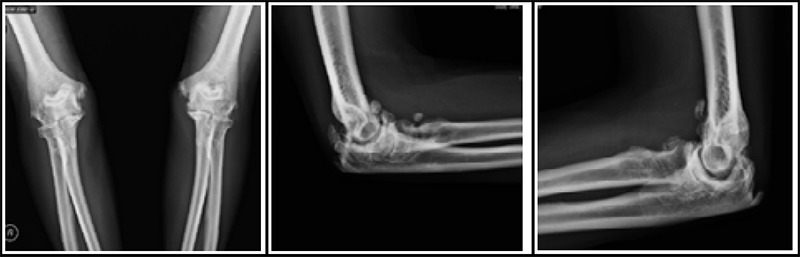

尺神经病变是一种常见的周围神经病变,肘管压迫是第二常见的上肢压迫综合征。神经节囊肿虽然罕见,但可导致肘管尺神经受压。在这里,我们提出了一个62岁的农民,长期患有糖尿病和血脂异常,他的内侧手指出现进行性疼痛和麻木,肘部屈曲加剧了这种情况。最初因汉森氏病被误诊并接受治疗。临床放射学评估显示左肘后内侧有多室囊性病变,压迫尺神经。手术切除神经节囊肿可减轻症状,但术后仍存在残余的运动缺陷。本病例强调了在肘管综合征鉴别诊断中考虑神经节囊肿的重要性,强调了在处理这种罕见病因时的诊断挑战和治疗考虑。

Ulnar neuropathy is a common peripheral neuropathy, with cubital tunnel compression being the second most frequent upper extremity compression syndrome. Ganglion cysts, though rare, can contribute to ulnar nerve compression in the cubital tunnel. Here, we present a case of a 62-year-old farmer with longstanding diabetes and dyslipidemia who experienced progressive pain and numbness in his medial fingers, exacerbated by elbow flexion. Initially misdiagnosed and treated for Hansen's disease. Clinico-radiological evaluation revealed a multiloculated cystic lesion in the posteromedial aspect of his left elbow, compressing the ulnar nerve. Surgical excision of the ganglion cyst alleviated symptoms, though residual motor deficits persisted postoperatively. This case underscores the importance of considering ganglion cysts in the differential diagnosis of cubital tunnel syndrome, highlighting the diagnostic challenges and therapeutic considerations in managing this rare etiology.